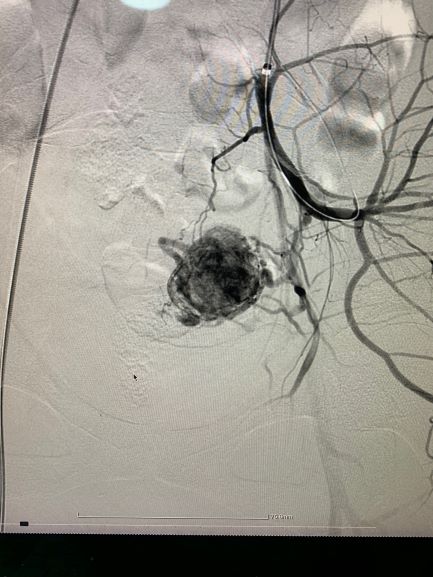

პაციენტს ჩაუტარდა მენჯის სელექტიური სუბტრაქციული ანგიოგრაფია და საშვილოსნოს არტერიის ანევრიზმის ტრანსკათეტერული არტერიული ემბოლიზაცია, რომელიც ენდოვასკულური მკურნალობის ოქროს სტანდარტია, რადგან ის არაინვაზიური, უსაფრთხო და მეტად ეფექტურია.

ოპერაციისშემდგომი მდგომარეობის შეფასების მიზნით და სისხლძარღვების სრული ოკლუზიის გამოსარიცხად პაციენტს ჩაუტარდა ემბოლიზაციის შემდგომი ანგიოგრაფიული და კომპიუტერული კვლევა, ადრეულ პოსტოპერაციულ პერიოდში და ოპერაციიდან 2 თვეში, რის შედეგადაც, პათოლოგია აღარ გამოვლინდა.